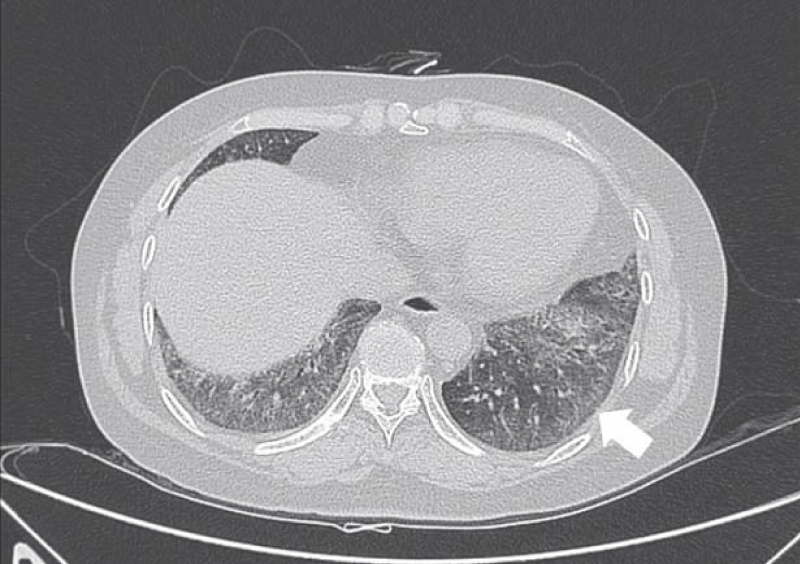

Figure 9: Different levels HRCT images from a 52 year-old male considered as LIP pattern.

The most common pattern in SSc-ILD was NSIP, accounted for 71.6% (83 patients); secondly was UIP, accounted for 25.9%, and 3 patients presented consistent with LIP.

The pathological characteristics of lymphocytic interstitial pneumonia (LIP) were diffuse interstitial lymphocyte infiltration and interlobular septal thickening. The feature of HRCT was the thin-walled (pellicle) cysts scattered in ground-glass opacities diffusely at both lungs [4].